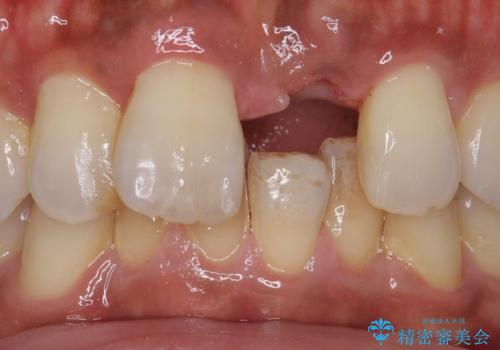

- 抜歯になった前歯を入れ歯で治療した症例です。

前歯部なので金属の留め金を使わない、審美性に優れたノンクラスプデンチャーによる補綴を行いました。